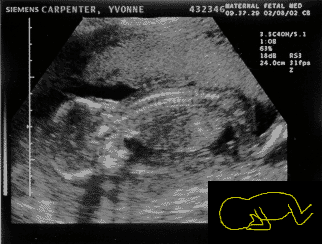

MY's looking good at 12 weeks Matt: The last two weeks were kind of fun. Luke or Kyla and I have had many conversations but so far they have been rather one sided. Yvonne has gotten in some really good runs and did not complain about nausea near as much. However there has been more complaints (from her) revolving around the three B’s — Butt, Belly, and Boobs. Make that the 4 B’s — BIG! She walks into the room stark naked and says things like, “my boobs are about to explode” butt (sic;-) enough of that! The ultrasound was again so cool I can’t even put it into words. Turns out that little animation at the top of the page is not too far off. The whole time the nurse was trying to take measurements arms were flying and legs were kicking. It was incredible! At one point right when an important measurement was about to be taken the MY baby turned it’s back to us. It was so funny! At any rate, all the measurements came out fine. Of course when it came time to record the video the MY baby seemed to take a nap. However the nurse jiggled the transducer and sure enough kick, wiggle, wiggle, turn the MY baby will soon be on DVD:-)

Yvonne: Phew!!!!!! I can’t believe we reached 12 weeks. It felt more like 12 years! The nausea is almost all gone but is being promptly replaced by a vicious appetite:-) I started watching the amount of food I eat and try not to get carried away using the pregnancy as an excuse to overeat. The plan is obviously NOT to starve the baby, but make the mom look somewhat human when this is all said and done! I feel like a cow — no exaggeration and the funny part is that I did not even gain the “big” weight yet. My breasts — can I talk about my breasts here? Just checking — they are HUGE! Melons come to mind. I look for tight bras to run in which is not hard given that everything I currently own is tight. I think I will go shopping for more comfortable underwear tomorrow… I can still fit in most of the current ones, but high school days come to mind when I try to put them on and it feels like trying to squeeze into a pair of jeans 2 sizes below your size (girls, remember that!) Today I actually had to put a pair back:-( Luke or Kyla seem to be doing fine and passed the first big test. I am sure that a future boyfriend/girlfriend/husband/wife will pay big money to see the video we got — it is so cute!!!